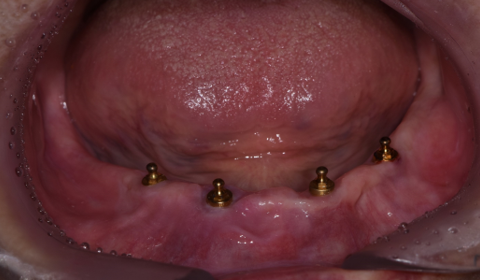

임플란트 식립

전체 틀니를 다시 제작하는 방법도 있지만, 최소한의 임플란트로 틀니를 잡아주는 치료를 결정하였습니다. 고령인 점 고려하여 무리가 가지 않게 무절개/최소절개로 4개의 임플란트를 식립하고 임플란트 똑딱이 장치를 이용하여 임플란트와 기존 쓰시던 틀니를 연결하였습니다.